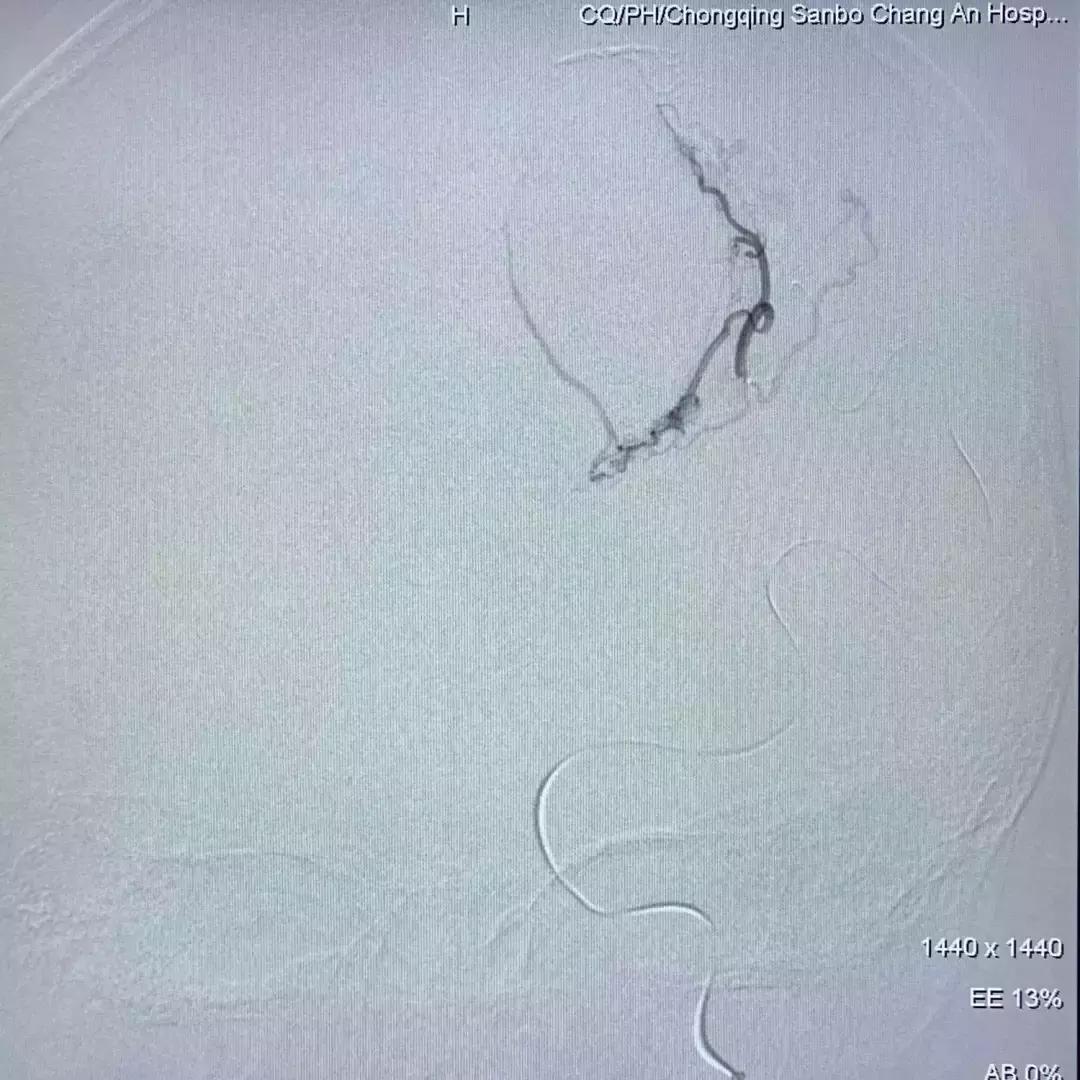

DSA脑血管造影提示脑血管畸形

从造影图上可以看到,畸形不大,但在脑子深部,位于功能区;正位像形似月牙,侧位看很弥散;而且均为终末细支或者细小侧支供血。经过和首都医科大学三博脑科医院刘加春教授远程会诊讨论,决定先给患儿实施栓塞治疗,这样既可以降低再出血概率,又可以尽量避免开颅手术造成的新的脑组织损伤,为小强的功能恢复最大限度创造条件。

如上几图只是刘加春教授寻找合适注胶动脉过程中的一部分